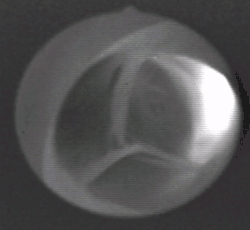

Frontal view of the aortic valve

The aortic valve is a valve in the heart of humans and most other animals, located between the left ventricle and the aorta. It is one of the four valves of the heart and one of the two semilunar valves, the other being the pulmonary valve. The aortic valve normally has three cusps or leaflets, although in 1–2% of the population it is found to congenitally have two leaflets.[1] The aortic valve is the last structure in the heart the blood travels through before stopping the flow through the systemic circulation.[1]

The aortic valve normally has three cusps however there is some discrepancy in their naming.[2] They may be called the left coronary, right coronary and non-coronary cusp.[2] Some sources also advocate they be named as a left, right and posterior cusp.[3][4] Anatomists have traditionally named them the left posterior (origin of left coronary), anterior (origin of the right coronary) and right posterior.[2]

The three cusps, when the valve is closed, contain a sinus called an aortic sinus or sinus of Valsalva. In two of these cusps, the origin of the coronary arteries are found. The width of the sinuses in cross-section is wider than the left ventricular outflow tract as well as wider than the ascending aorta. The junction of the sinuses with the aorta is called the sinotubular junction. The aortic valve is located posterior to the pulmonary valve and the commissure where the anterior two cusps join together points toward the pulmonary valve. It is these two sinuses that contain the origin of the coronary arteries. In the congenital disease known as transposition of the great arteries, these two valves are reversed (the anterior valve is the aortic valve) and the origin of the coronaries still follows this "rule" that the origins are in the sinuses facing the pulmonary valve.

The term "semilunar" refers to an approximate half-moon shape of the valve leaflets.[5]